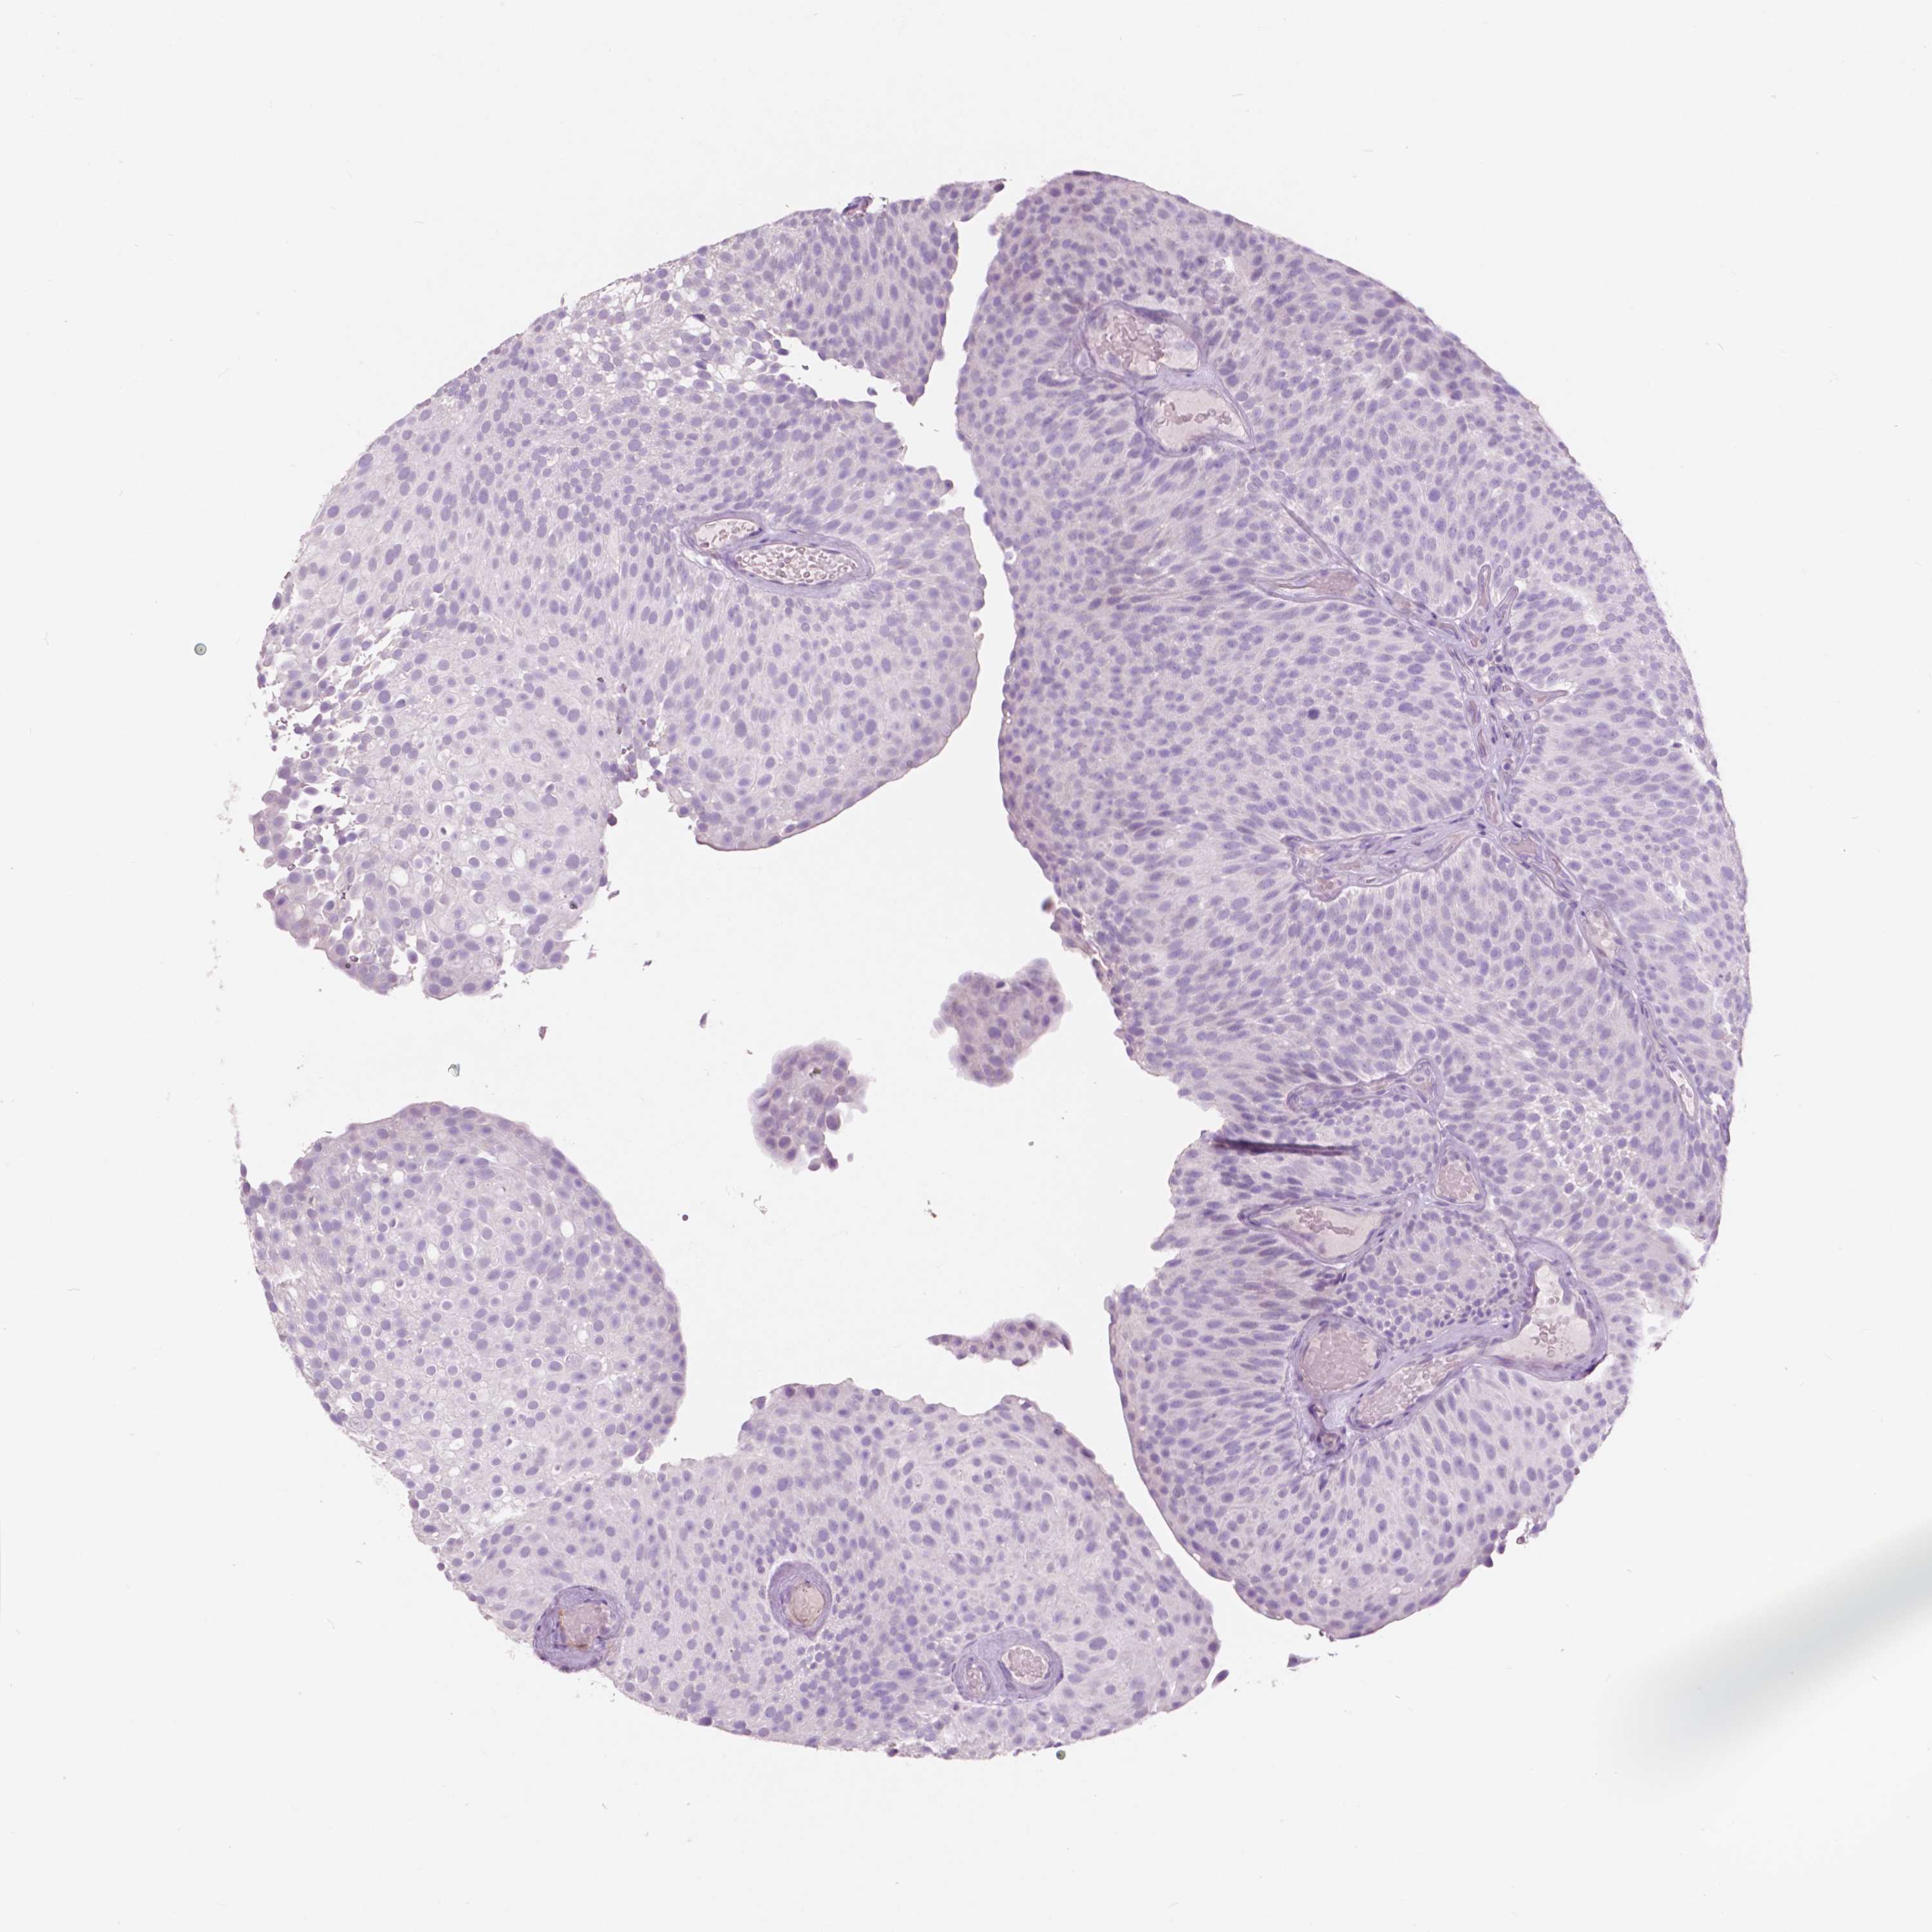

UROTHELIAL CANCER - Protein expressioni

A mouse-over function shows sample information and annotation data. Click on an image to view it in a full screen mode. Samples can be filtered based on level of antibody staining by selecting one or several of the following categories: high, medium, low and not detected. The assay and annotation is described here.

Note that samples used for immunohistochemistry by the Human Protein Atlas do not correspond to samples in the TCGA dataset.

Antibody stainingi

Antibody staining in the annotated cell types in the current human tissue is reported as not detected, low, medium, or high, based on conventional immunohistochemistry profiling in selected tissues. This score is based on the combination of the staining intensity and fraction of stained cells.

Each image is clickable and will lead to virtual microscopy that enables deeper exploration of all samples and also displays staining intensity scores, fraction scores and subcellular localization as well as patient and tissue information for each sample.

Antibody HPA023072

Urothelial carcinoma, Low grade

Urothelial carcinoma, High grade